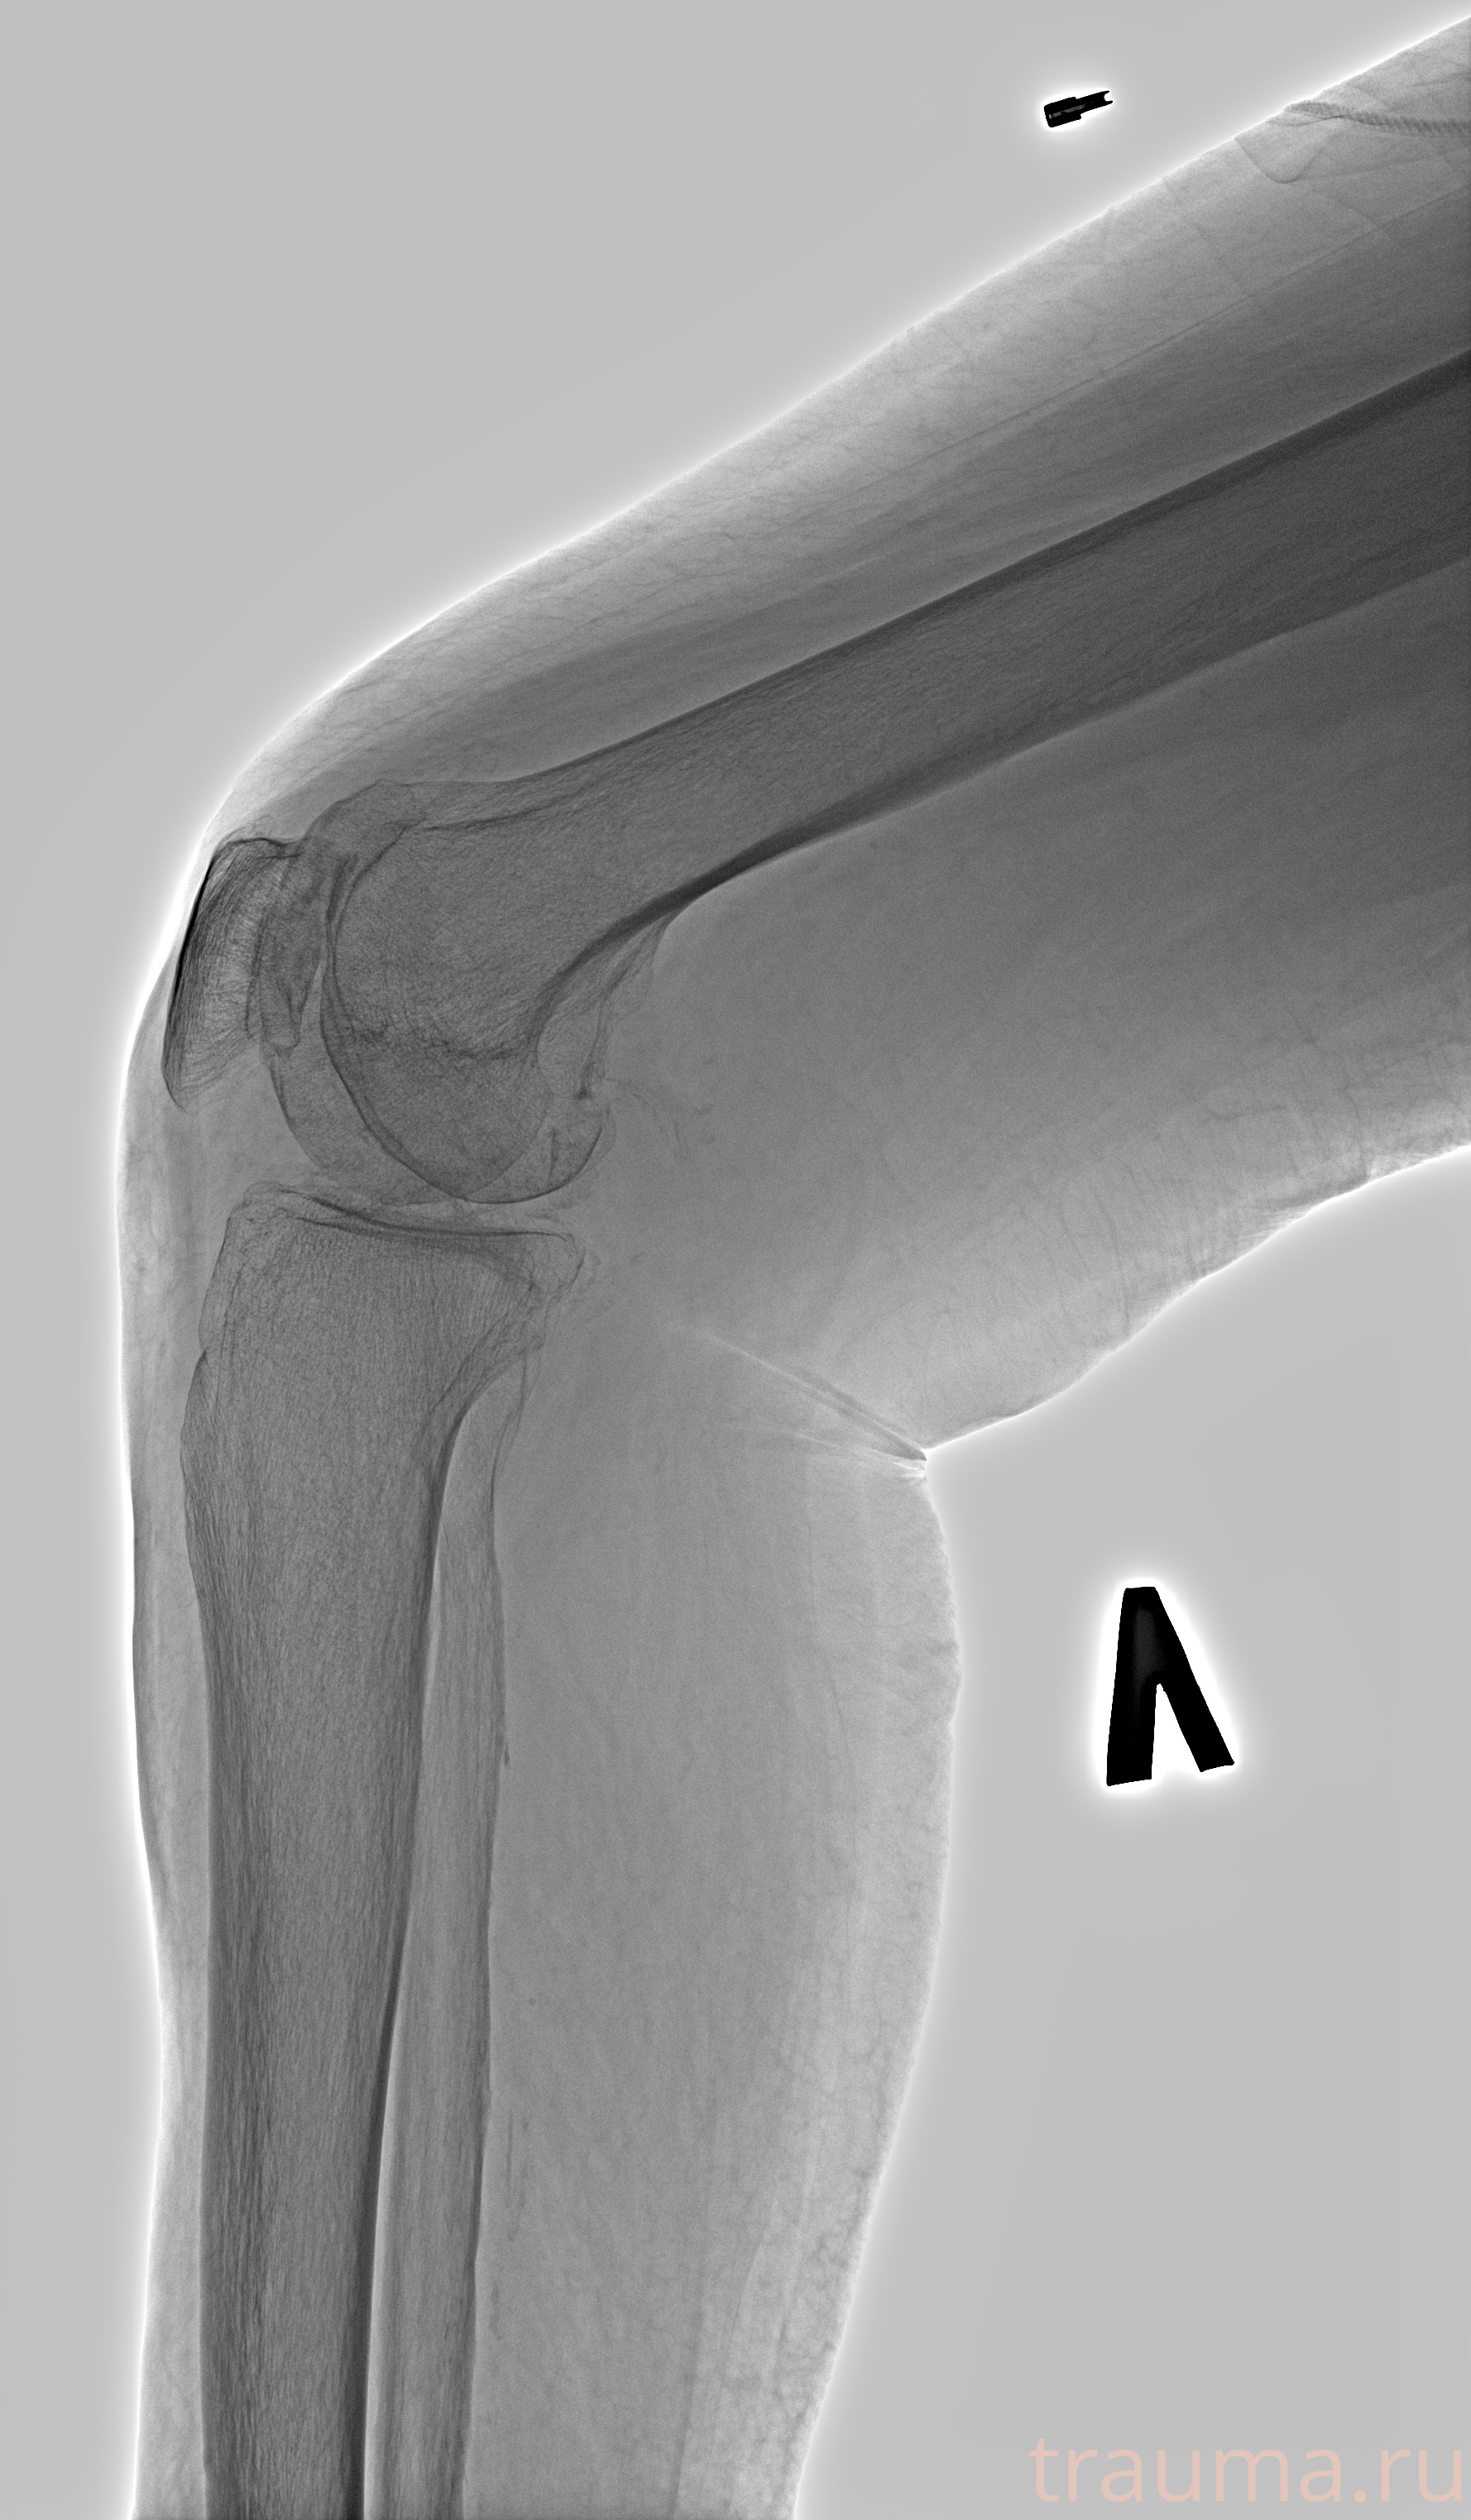

Рентгенограммы

Рентген на дому: по вашему адресу приезжает врач-рентгенолог, травматолог-ортопед с мобильным рентгеновским аппаратом, проводит диагностику травмы или заболевания, делает необходимые рентгенограммы, дает рекомендации по дальнейшему лечению. Получить качественные снимки в домашних условиях возможно благодаря уникальной методике, разработанной МосРентген Центром для института  Склифосовского